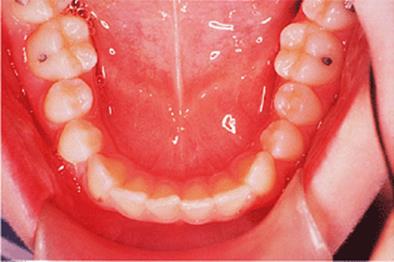

Before discussing functional appliances in detail, Fig. 18.1 gives an overview of this type of functional appliance in clinical use. This patient has a Class II division 1 malocclusion of the type for which functional appliances are very suitable, and for which they have been used for many years.

There are a number of important features to note which will be discussed further later in the chapter. First, the patient is still growing and the signs are that her pattern of facial growth is likely to be favourable. Although the skeletal pattern is Class II, the vertical relationships are close to average and the direction of mandibular growth is likely to be a mild forward rotation (see Chapter 4) which is favourable to the correction of a Class II malocclusion. Second, the soft tissue morphology is favourable despite the lips being incompetent, with the lower lip resting behind the upper incisors. The lower lip line is above the level of the upper incisal edges, and after the overjet has been reduced the lower lip will rest labially to the upper incisors, so helping to resist any tendency for relapse of the overjet. Third, the arches are well aligned — functional appliances have no mechanism for treating irregularities of alignment of the teeth.

Fig. 18.1. (a) This 12-year-old girl had a skeletal II facial pattern and average facial proportions. The lips were incompetent with the lower lip lying below the upper incisors at rest. (b), (c) She had a Class II division 1 malocclusion with an overjet of 10 mm, the overbite was increased and complete, and the molar relationship was Class II on both sides. (d), (e) The upper and lower arches were well aligned. (f) A functional appliance (an activator) was fitted. (g) The corrected occlusion with Class I incisor and molar relationships. (h) The patient's facial profile at the end of treatment.